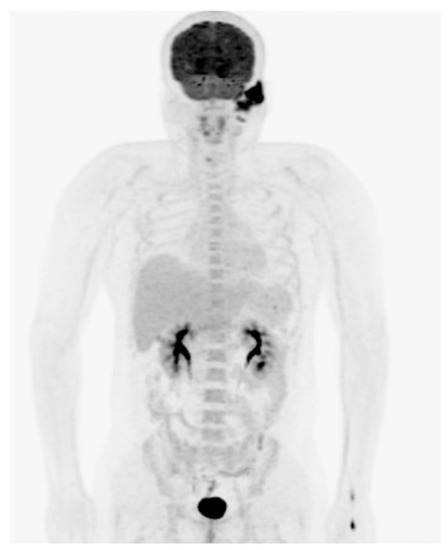

| Gomaa et al., 2010 | Female | 47 | Otalgia, EAC swelling | No osseous erosion | Radio-uptake | CD4, CD5, CD30 | NA | RT |

| Present case, 2021 | Male | 34 | Painless mass | No osseous erosion | Radio-uptake | CD3, CD30 | Positive | CCRT |